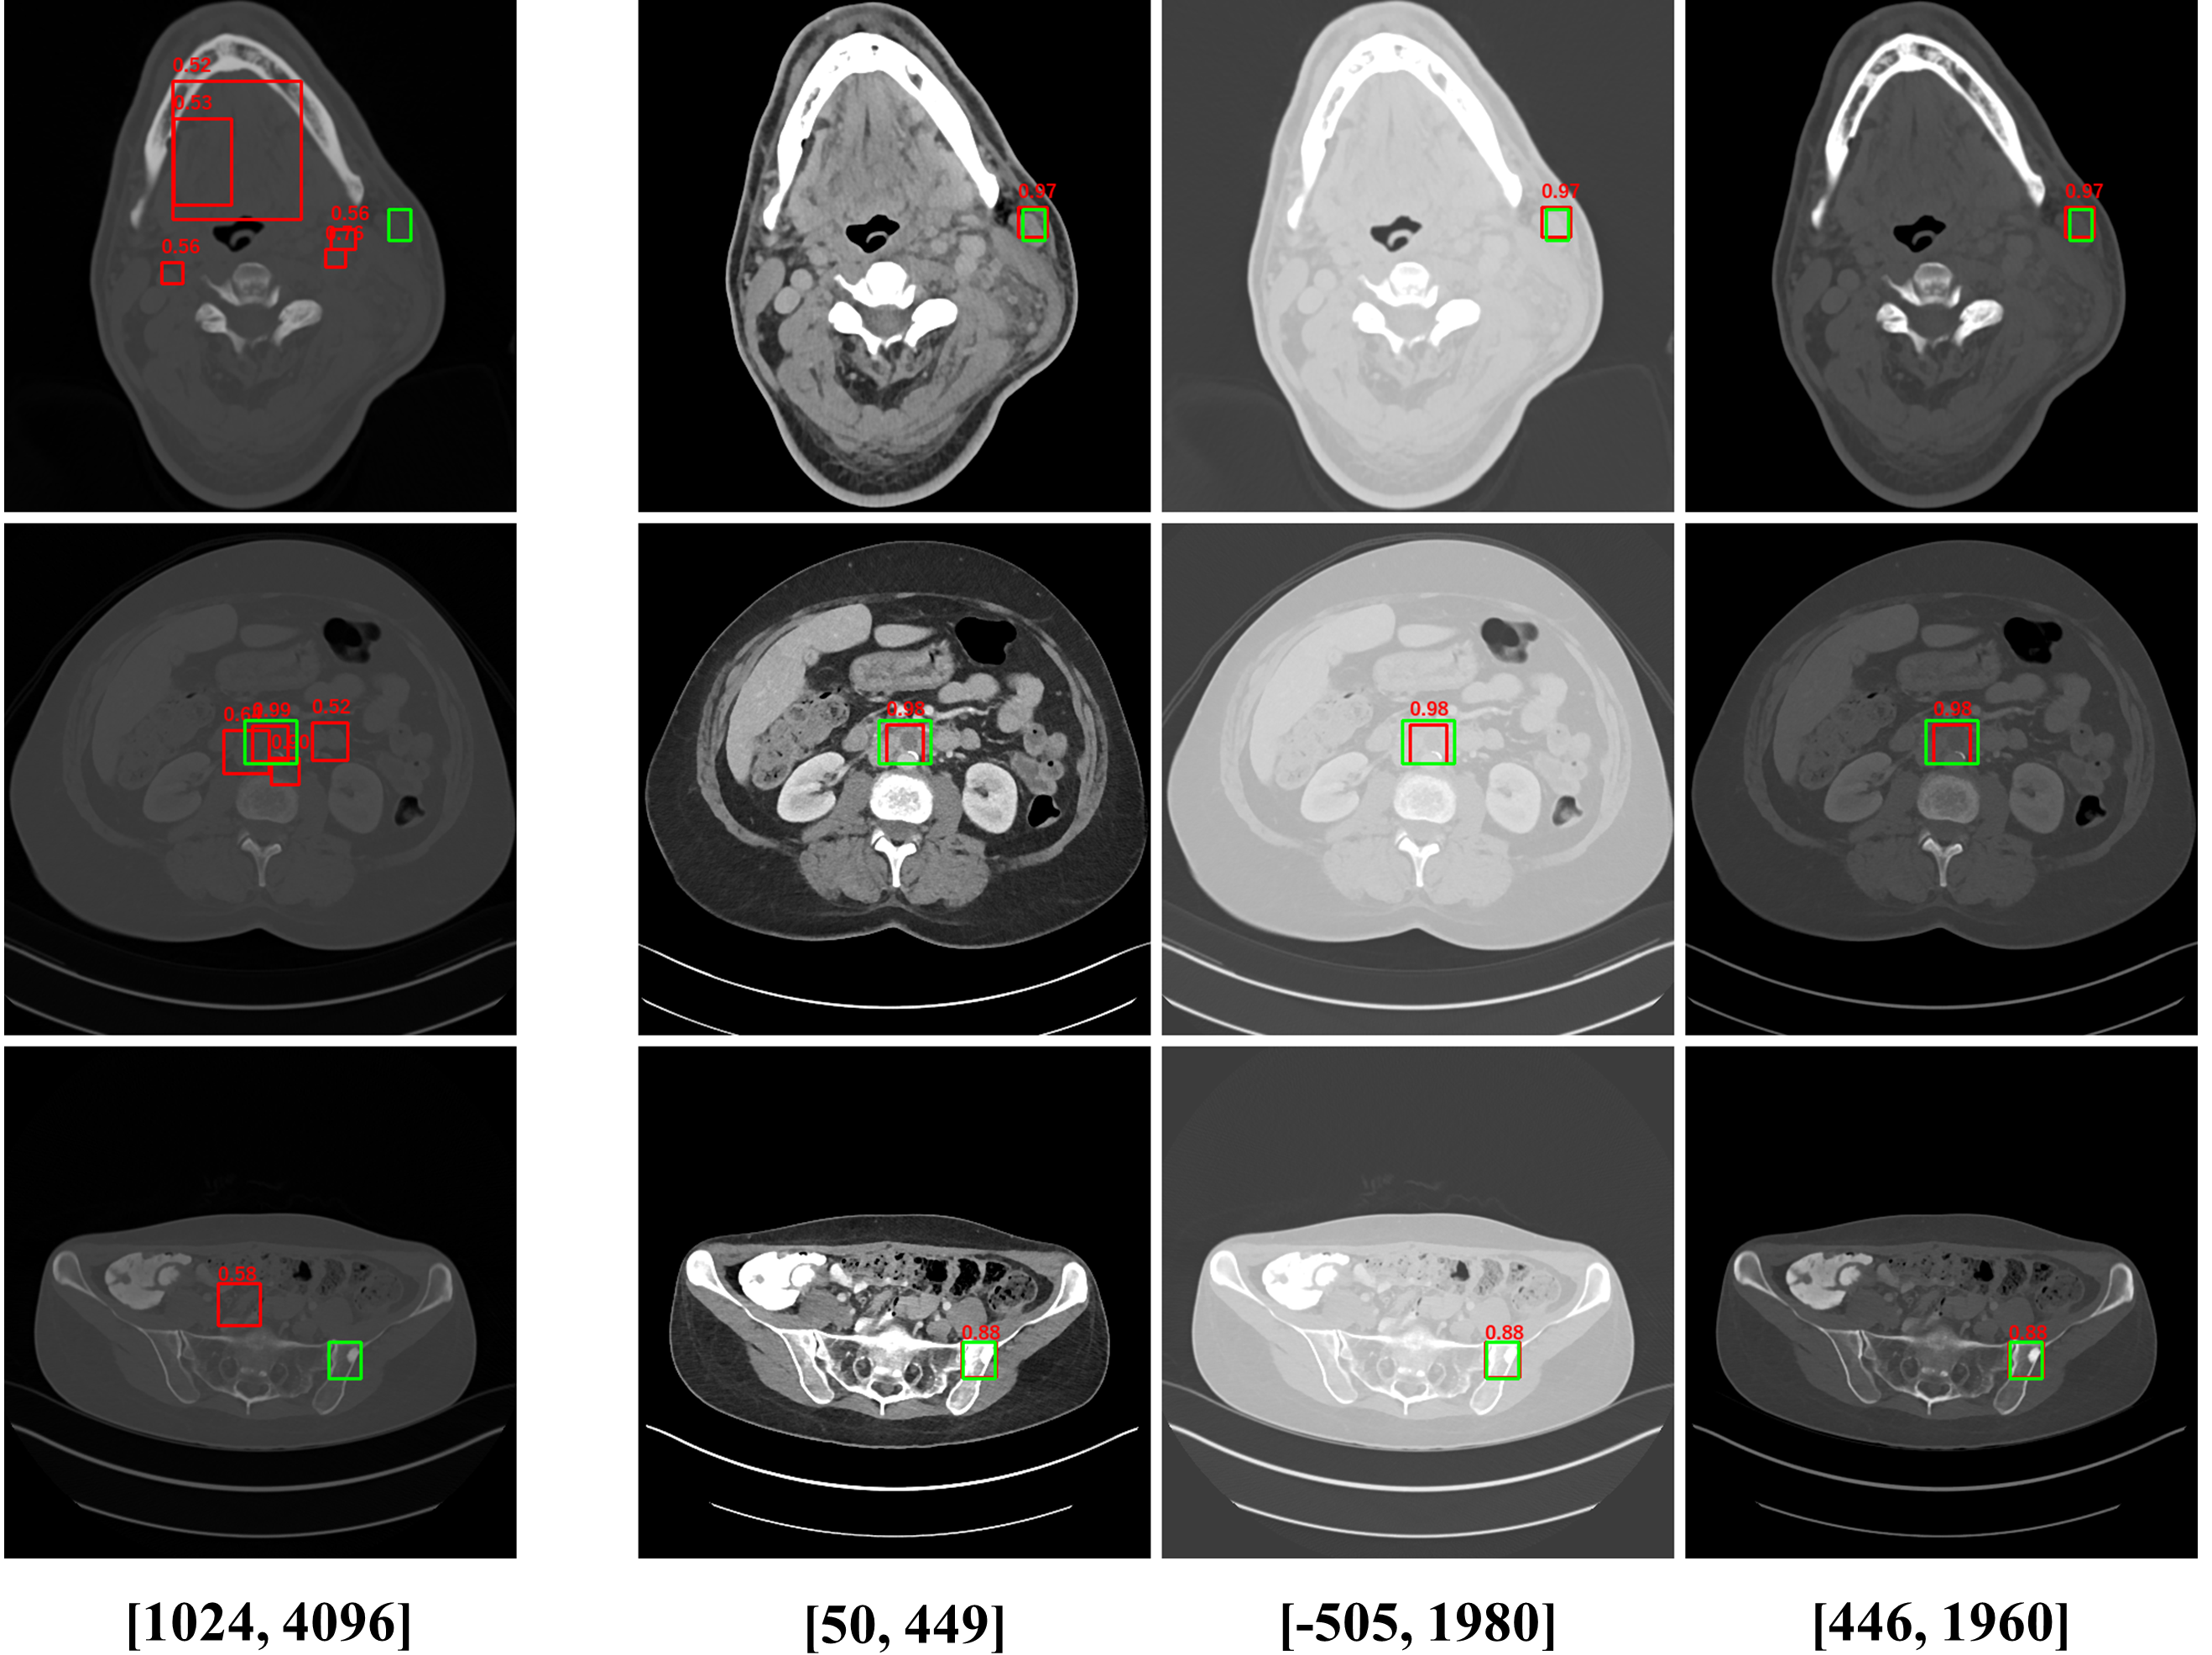

Figure 1: CT images under different window level and window width. (a) is the image used in 3DCE. (b),(c),(d) are the multi-view images used in our MVP-Net.

To accommodate for network input, previous studies [5, 6] use a significantly wide window222Windowing, also known as gray-level mapping, is used to change the appearance of the picture to highlight particular structures. to compress CT’s 12bit Hounsfield Uint (HU). However, this would severely deteriorate the visibility of lesions as a result of degenerated image contrast, as shown in Fig.1(a). In the clinical practice, fusing information from multiple windows are effective in improving the accuracy of detecting subtle lesions and reducing false positives (FPs). During visual inspection of the CT images, radiologists would combine complex information of different inner structures and tissues from multiple reconstructions under different window widths and window levels to locate possible lesions. To imitate this process, we propose to extract prominent features from three frequently examined window widths and window levels and capture complementary information across different windows with an attention based feature aggregation module.

The multi-view input for the MVP-Net is composed of multiple reconstructions under different window widths and window levels. Specifically, we adopt k-means algorithm to cluster the recommended windows (labeled by radiologists) in the DeepLesion dataset and obtain three most frequently inspected windows, whose window levels and window widths are [50,449]50449[50,449], [505,1980]5051980[-505,1980] and [446,1960]4461960[446,1960] respectively. As shown in Fig.1, these clustered windows approximately correspond to the soft-tissue window, lung window, and the union of bone, brain, and mediastinal windows respectively.

We also perform a case study to analyze the importance of multi-view modeling. As shown in Fig. 3, the model indeed benefits from the multi-view modeling: the lesions that are originally indistinguishable in the view of 3DCE due to the wide window range and lack of contrast, now becomes distinguishable under the view of appropriate windows. Thus our model presents better identification and localization performance.

Refer to caption

Figure 3: Case study for 3DCE (left-most column) and attention based multi-view modeling (the other three columns). Green and red boxes correspond to ground-truths and predictions respectively.